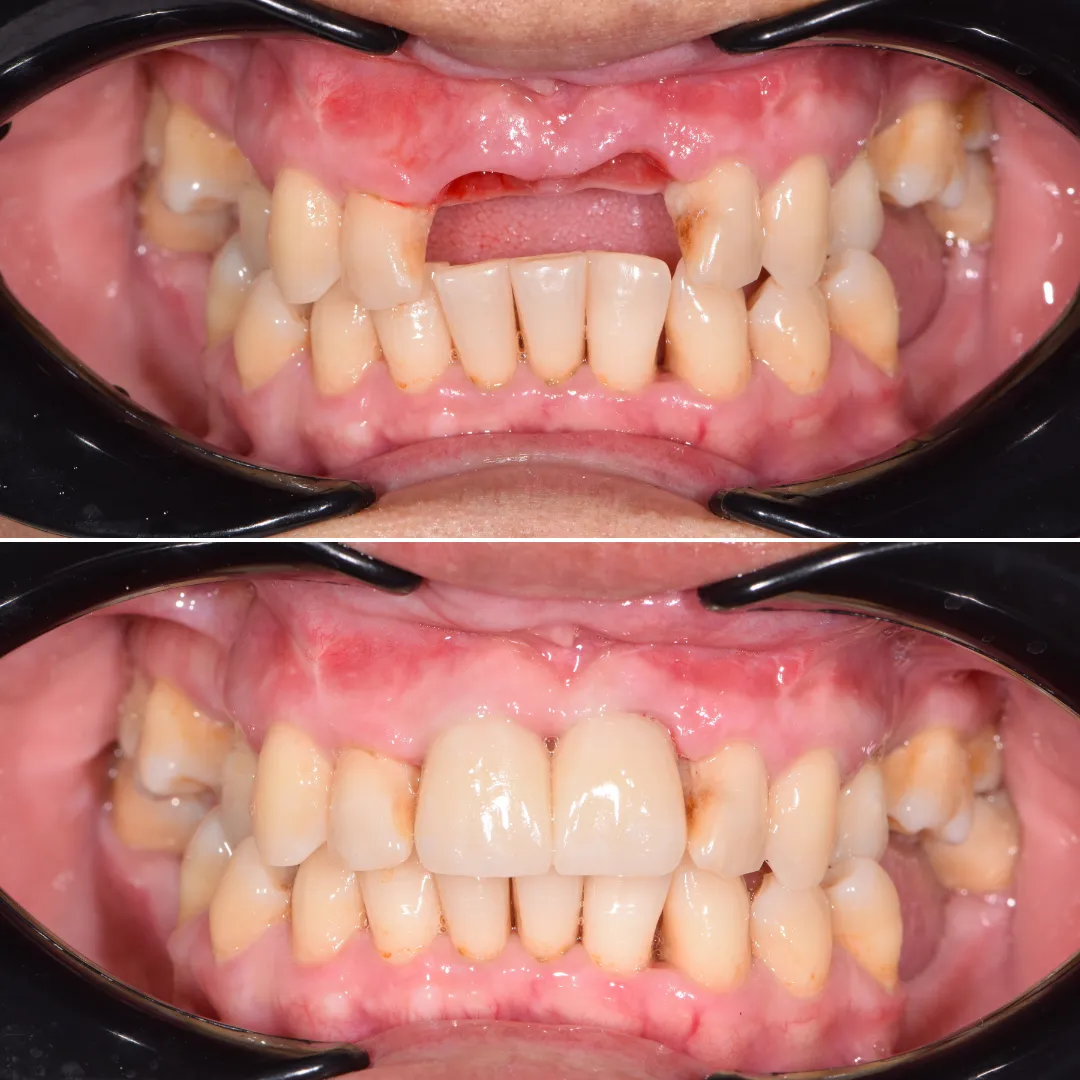

Resultado implante dental